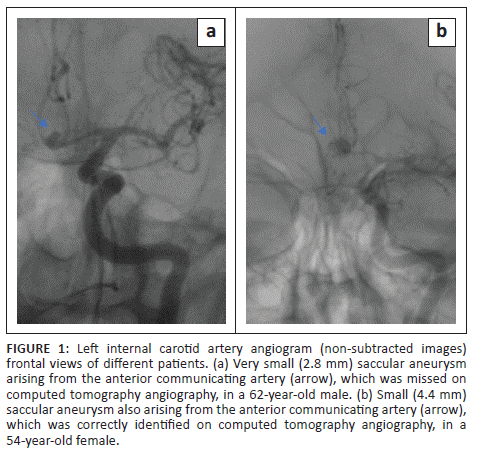

Statistical analysis regarding aneurysm size and location was performed on per patient-basis, which was 94 aneurysms considered to be ruptured in 94 patients. The aneurysm size ranged from 1 mm to 30 mm, with a median of 5.8 mm (IQR: 4.0-8.3). The frequency distribution of aneurysms by size group as determined by DSA and the respective CTA detection efficiency are demonstrated in Table 3. The large and giant aneurysms were all correctly identified on CTA; however, they were very few in number (6/94), therefore, were excluded from comparative statistical analysis. Computed tomography angiography missed 7 of 10 (70%) very small aneurysms (< 3 mm) resulting in a poor sensitivity of 30%. The CTA sensitivity (30%) for very small aneurysms (< 3 mm) was significantly poor compared with the 3-5 mm (small size) group, the > 5 mm to < 15 mm (medium-sized) group and the overall CTA sensitivity (80%) (p = 0.024). Figure 1 shows a very small and a small aneurysm.

Diminished CTA sensitivity for very small aneurysms (≤ 3 mm) is well documented in the literature,11,15,17 which is congruent to this study. In contrast Lu et al. demonstrated good CTA sensitivity even for aneurysms < 3 mm in size using dual energy CTA.12 Some authors reported no difference in CTA sensitivity for anterior versus posterior circulation aneurysms.11,12 This finding is supported by this study, even though the aneurysm frequency proportions were markedly skewed towards the anterior circulation. Several studies reported lower CTA sensitivity for locations close to the bony base of skull such as the ICA14,15 and PComm.19 The latter was congruent with the findings of this study, which demonstrated significantly lower PComm sensitivity (56%) compared with other major anterior circulation locations. The ICA location however did not show significantly compromised CTA sensitivity in this study (Figure 2).